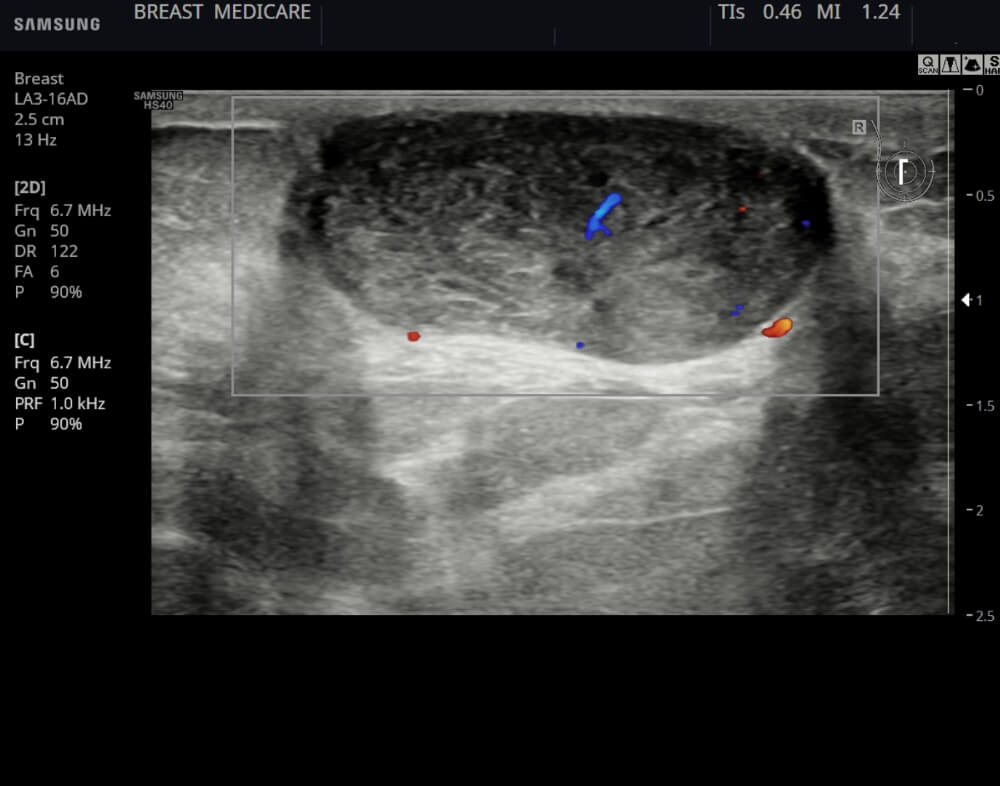

Απεικονιστικά έχουν χαρακτηριστική εικόνα στο υπερηχογράφημα.

Η διάγνωσή τους στις νεότερες ηλικίες γίνεται με βάση το ιστορικό εμφάνισης και εξέλιξης, την κλινική εικόνα και τα υπερηχογραφικά ευρήματα.